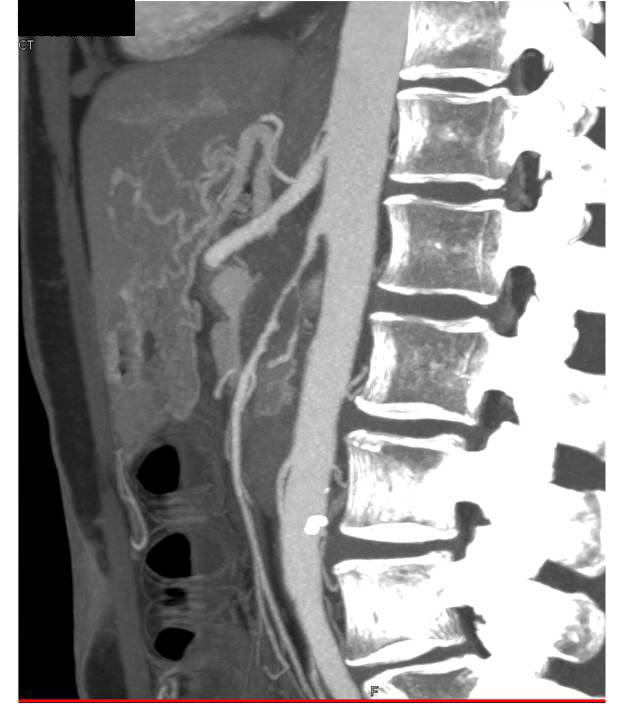

Neuroendocrine Tumor of the Pancreatic Head with CTA Mapping